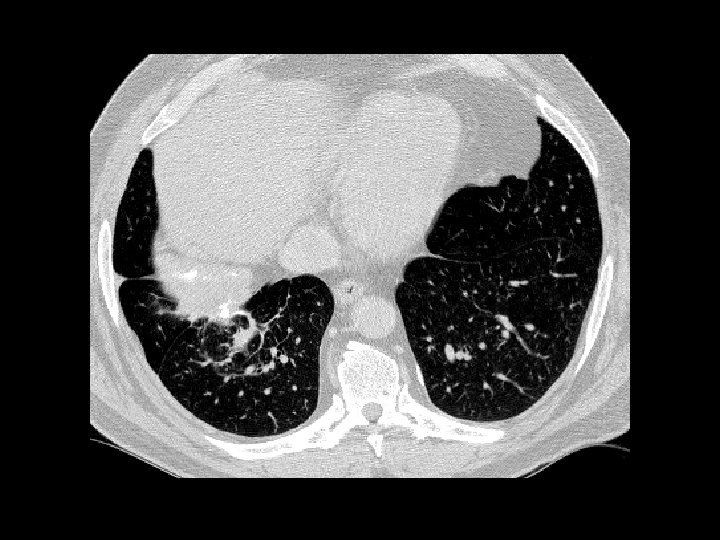

Cystic fibrosis • Findings: – Diffuse bronchiectasis – hyperinflation – mild enlargement of central pulmonary arteries • ddx: – Immotile ciliary syndrome – immunodeficinecy & chronic infections